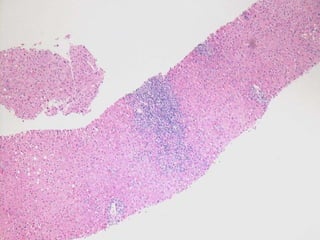

BS09-15303  Clinical history: 56 yo, female. elevated transaminase and anti-mitochondrial antibody.

BS09-15303  Dx: Primary biliary cirrhosis, Scheuer stage 1/4 (Diagnostic biopsy).

BS09-15303 Clinicalhistory: 56 yo, female. elevated transaminase and anti-mitochondrial antibody.

BS09-15303 Dx:Primary biliary cirrhosis, Scheuer stage 1/4 (Diagnostic biopsy).